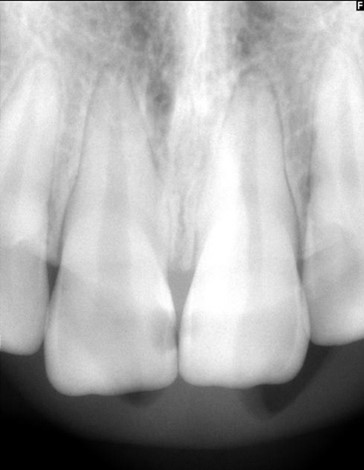

Vurder kontrasten på denne optagelse.

kontrasten vurderes som lav til moderat

der er kun små forskelle mellem gråtonerne

emalje og dentin fremstår forholdsvis ens

lamina dura ses kun svagt (rodlinjen)

det trabekulære knoglemønster er utydeligt

strukturerne fremstår lidt udjævnede og mindre klart afgrænsede